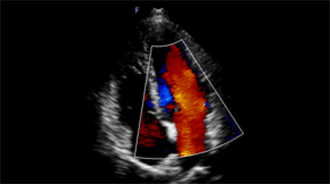

适用于成人心脏

频率高于传统心脏探头,更适用于婴幼儿心脏